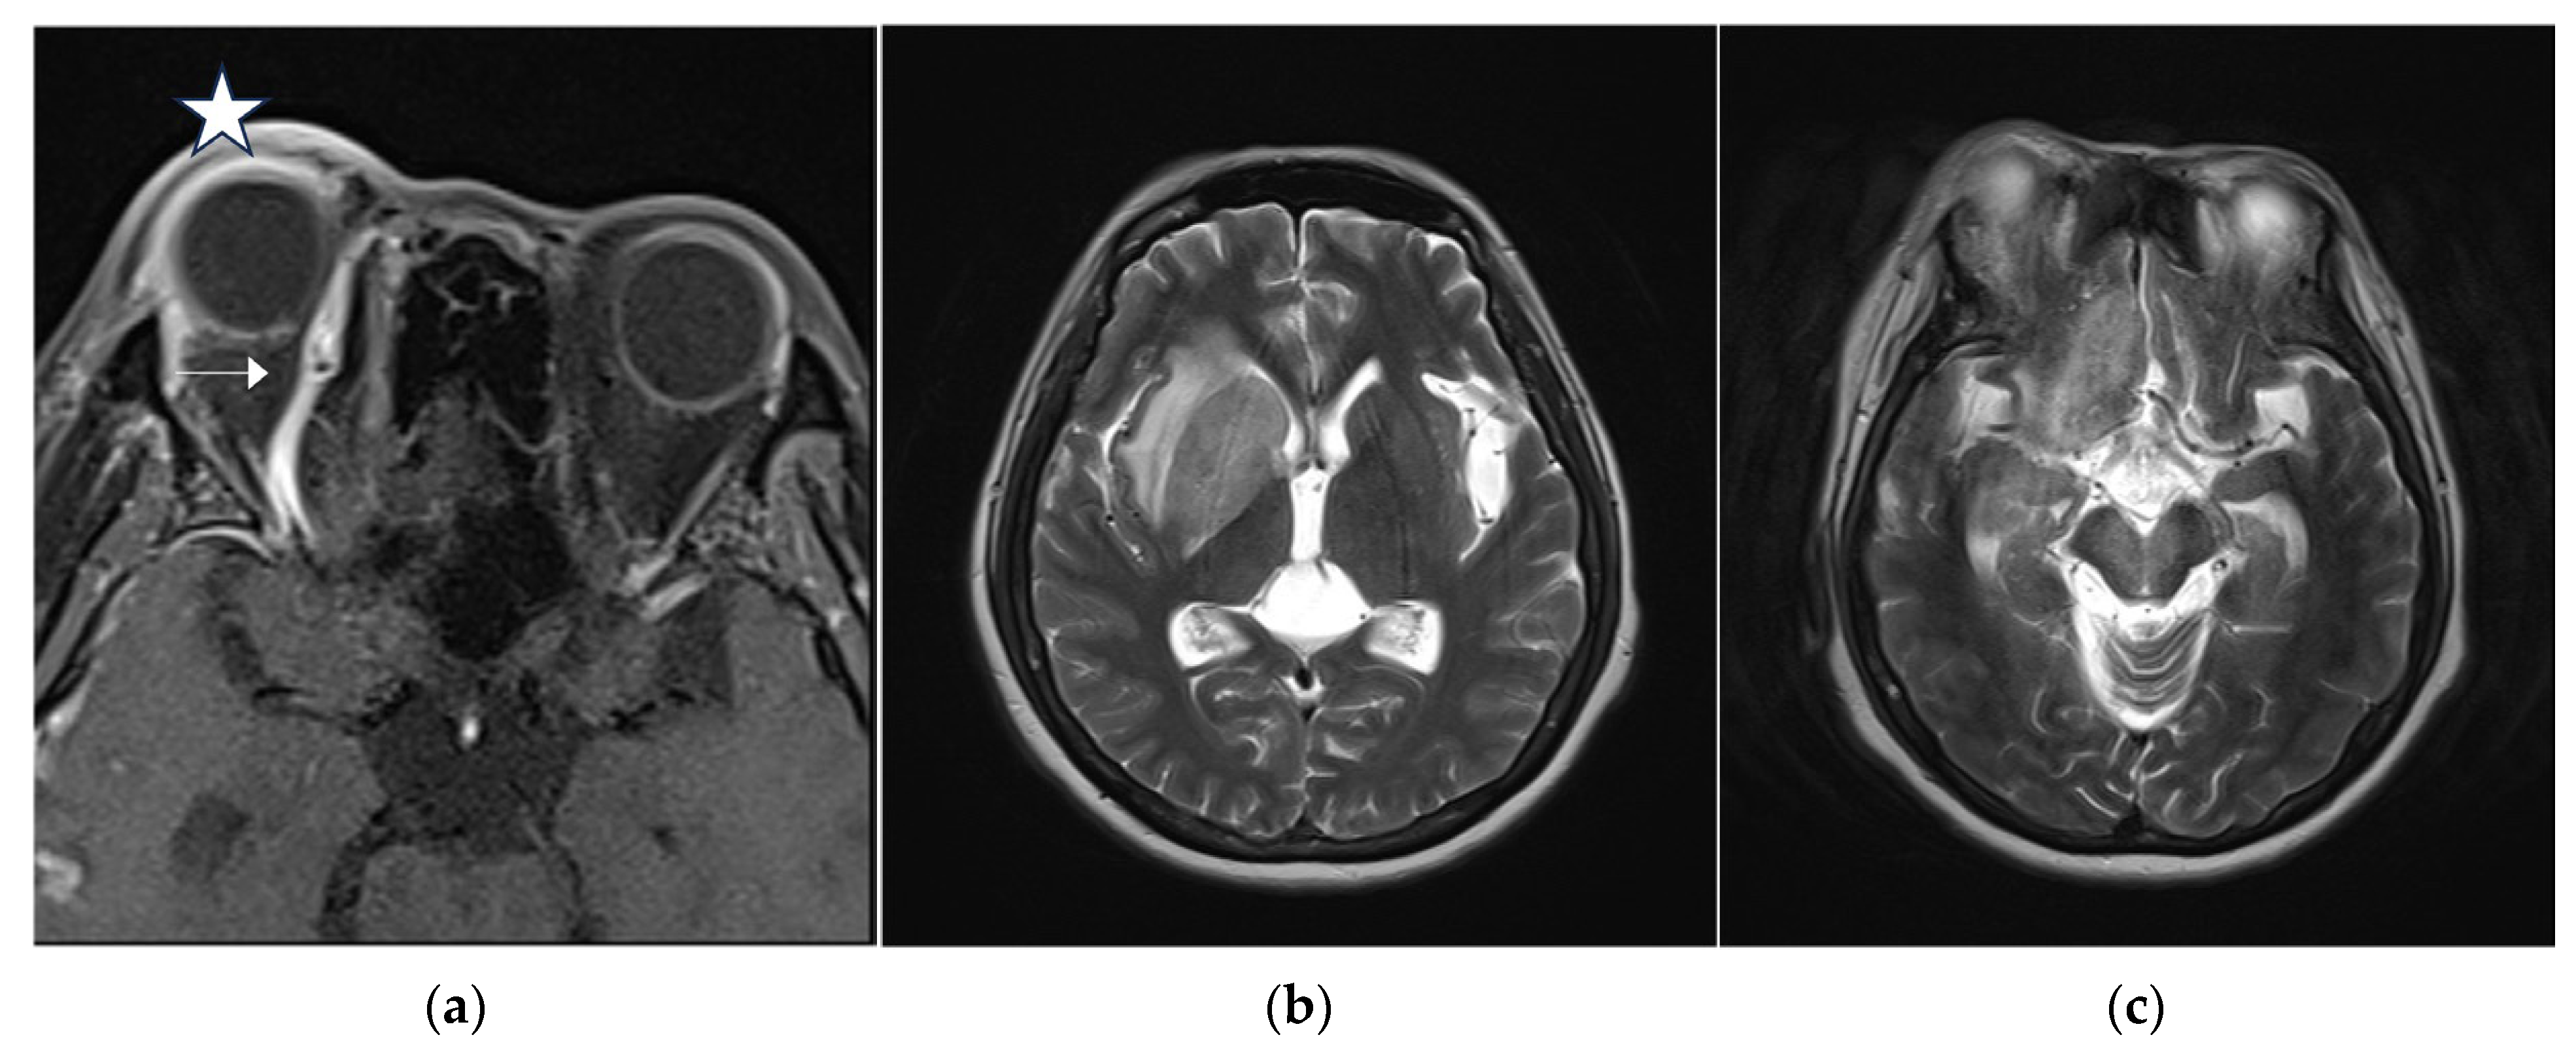

2. Case Report

| Coronal cut: T2-weighted imaging Fast Recovery Fast Spin Echo (T2 frFSE) Axial cut: T2 frFSE, T1-weighted imaging Fluid-Attenuated Inversion Recovery (T1 FLAIR), T2-weighted imaging FLAIR Fat Saturation (T2 FLAIR fs) Diffusion-Weighted Imaging (DWI) b1000 3D TOF MRA: Three-dimensional Time of Flight Spoiled Gradient Recalled Echo Fat Saturation HyperSense ( 3D TOF SPGR FS HyperSense) Post-contrast: Contrast-Enhanced Fat Saturation Three-dimensional Sagittal T1-weighted imaging Cube (C+ fs 3D SAG T1 Cube), C+ AXI T1 SPGR, C+ SAG T1 SPGR CEMRA: Contrast-Enhanced Magnetic Resonance Angiography CEMRV: Contrast-Enhanced Magnetic Resonance Venography |